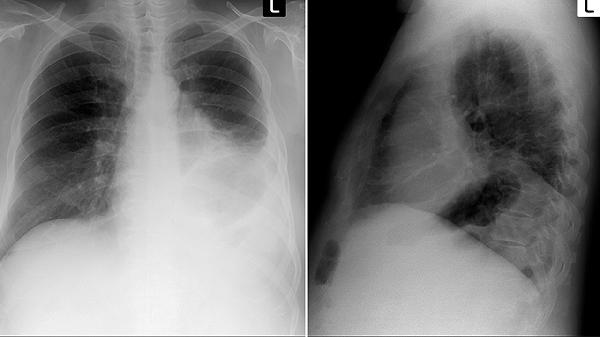

双肺多发结节可能与肺结核、肺转移瘤、肺真菌感染、结节病、尘肺等疾病有关。肺部结节通常表现为咳嗽、胸痛、呼吸困难等症状,建议及时就医明确诊断。

发现双肺多发结节应尽早就医完善检查,包括胸部CT、肿瘤标志物、结核菌素试验等。日常生活中需戒烟,避免接触粉尘和污染空气,保持适度运动增强免疫力。饮食上注意营养均衡,适当增加优质蛋白和维生素摄入。遵医嘱定期复查,观察结节变化情况。